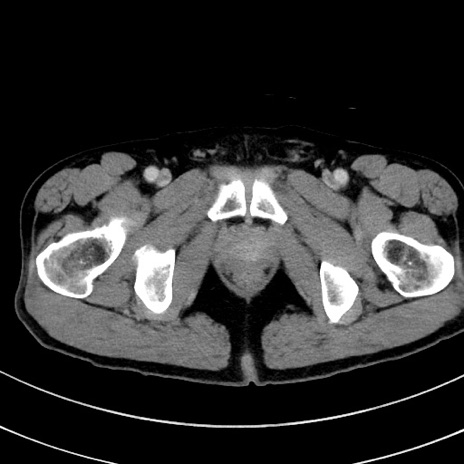

症例8(横断像)

冠状断像

【症例】 60歳代男性

【主訴】 黒色吐物

【現病歴】 4日前から嘔気自覚、2日前の朝食後にも嘔気あり、自分で手で嘔吐反射起こし嘔吐したところ血が混ざっていたため受診。

【既往歴】 5年前汎発性腹膜炎を伴う急性虫垂炎で手術、高血圧、前立腺肥大症、高脂血症

【身体所見】 腹部正中に手術癩痕あり 腹部平坦・軟圧痛なし膨満感あり

【データ】WBC 8400、CRP 4.54